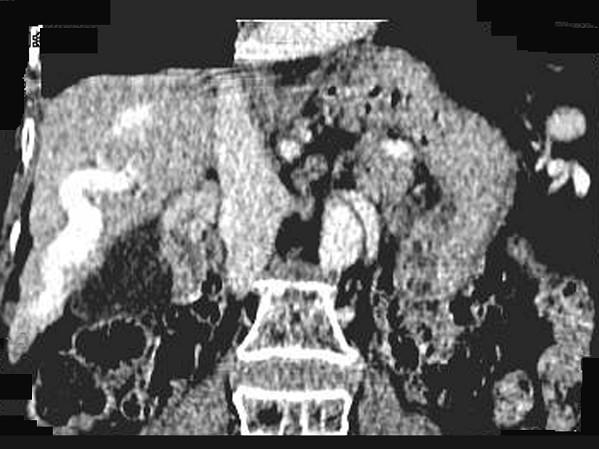

问题 女,70岁,发现乙型肝炎10年,3年前CT诊断为肝硬化,CT检查见图,最可能的诊断是 ( )

选项 A.肝癌 B.肝硬化、肝血管瘤 C.肝硬化、门脉瘤样扩张 D.肝门脉畸形 E.肝转移瘤、门脉扩张

答案 C